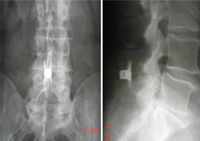

Implantes dinámicos percutáneos para lumbalgia crónica por síndrome facetario

Fusión TLIF percutánea con anestesia local e incisión de sólo 12 mm